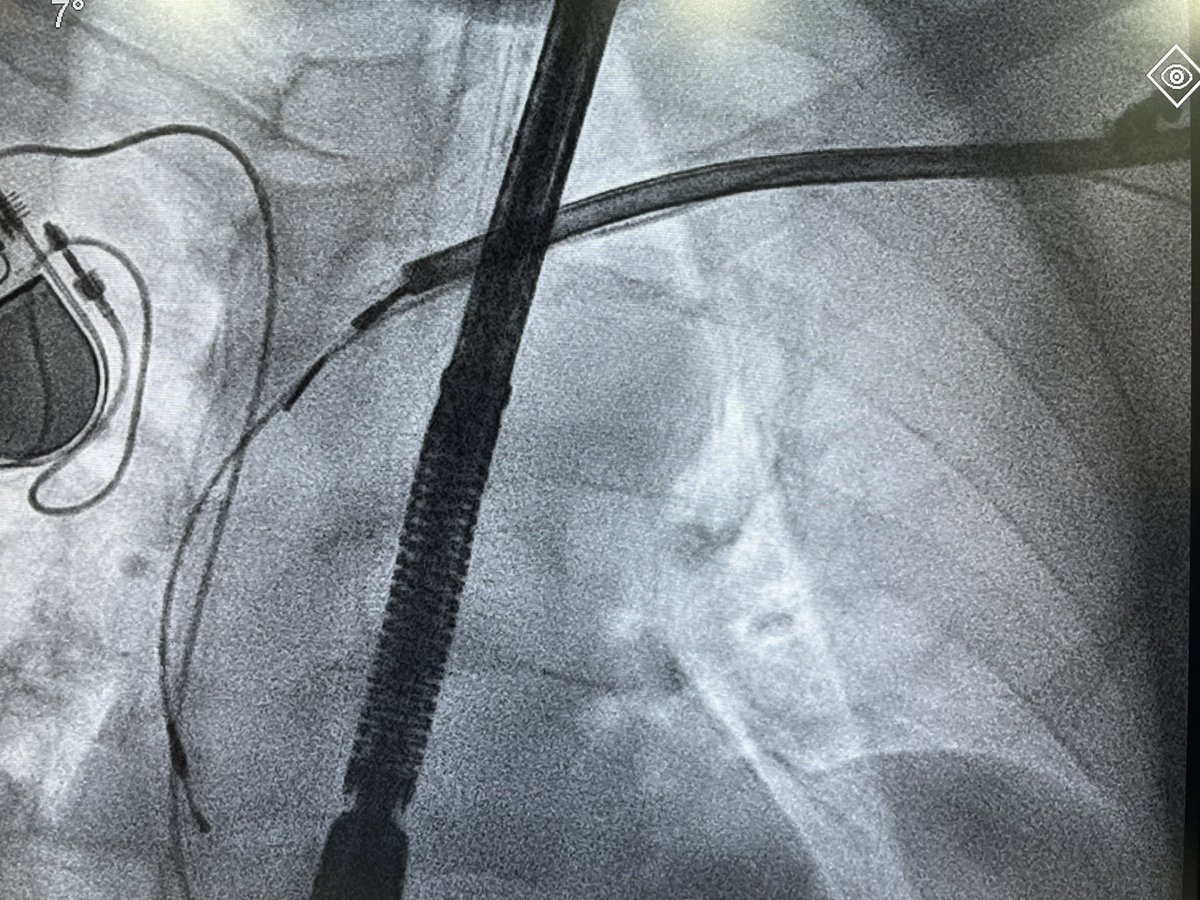

Dual chamber Leadless AVEIR pacemaker at Apollo Chennai - first in Tamilnadu and Apollo Group. - innovative, revolutionary, minimally invasive solution that ensures faster recovery and lasting comfort with physiological pacing. @Pacemaker @Apollo_Chennai @AbbottNews